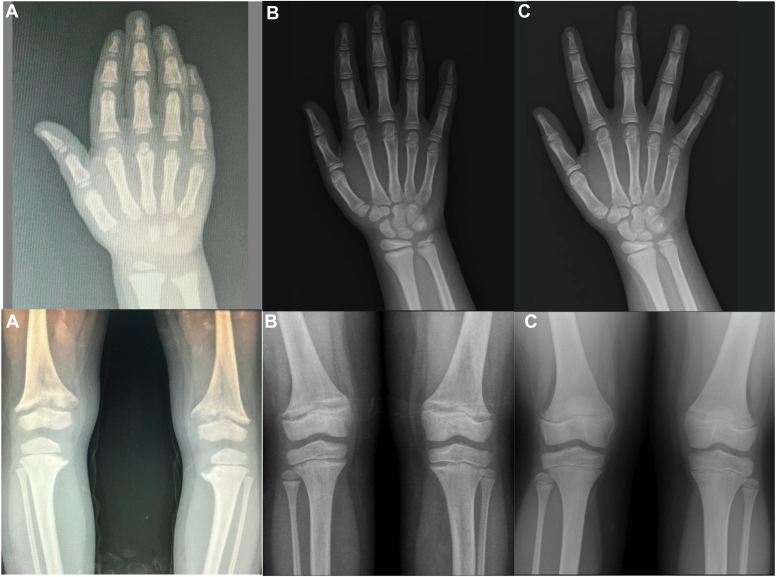

A female patient was diagnosed with XLH at 3 years old and received regular calcitriol and sodium-potassium phosphate treatment until age six. During this period, she showed increased growth velocity and improved height Z-score (from −2.38 SD to −1.95 SD). At 6 years and 11 months, she was diagnosed with idiopathic CPP, marked by thelarche, a growth spurt, and advanced bone age, resulting in a decreased predicted final height Z-score. She began pubertal blockade with leuprolide acetate and transitioned from conventional XLH treatment to burosumab. The combination of these treatments led to stabilized bone age, normalized growth velocity, and improved final height prediction without side effects or negative impacts on bone health during treatment.